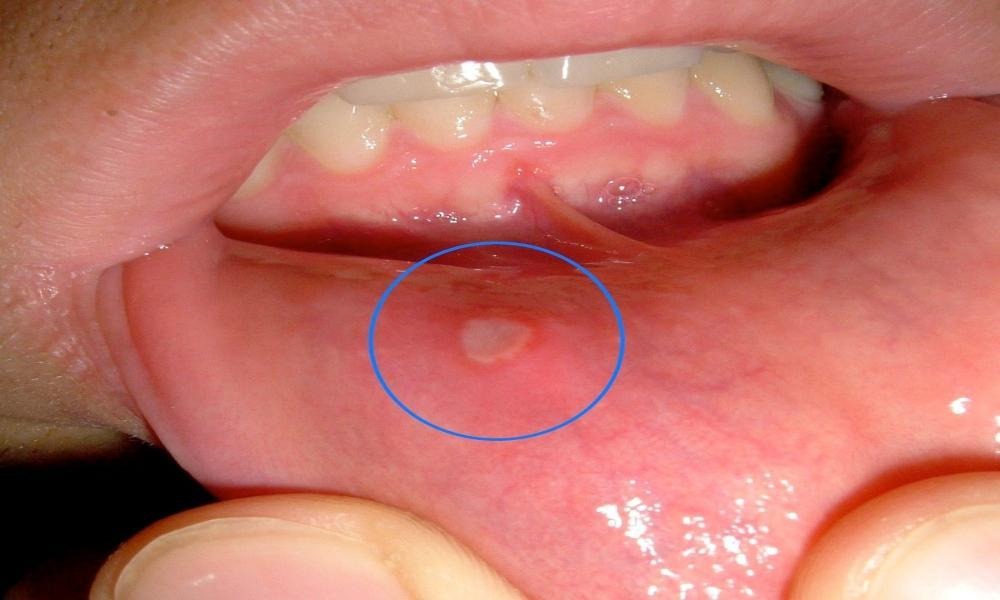

તમે જોયું હશે કે કેટલાક લોકો મોઢામાં ચાંદાથી પરેશાન હોય છે. પરંતુ, કેટલાક લોકોના મોઢામાં સફેદ ફોલ્લા પડી જાય છે જે એ સંકેત આપે છે કે તમારા શરીરમાં ઝડપથી ફેરફારો થઈ રહ્યા છે. ઉપરાંત, આ એક સંકેત છે કે તમે જીવનશૈલી અને આહાર સંબંધિત ખામીઓથી પીડાઈ રહ્યા છો. ઉપરાંત, તે ખૂબ જ ખરાબ જીવનશૈલી જીવી રહ્યો છે. તો ચાલો જાણીએ મોઢામાં સફેદ ફોલ્લા થવાનું કારણ.

મોઢામાં સફેદ ફોલ્લા થવાના કારણો:

તણાવ- તણાવને કારણે તમારા શરીર પર સફેદ ફોલ્લા પડી શકે છે. ખરેખર, જ્યારે આપણે ખૂબ વધારે તણાવ લઈએ છીએ, ત્યારે શરીર આલ્કલાઇન બની જાય છે અને શરીરની ગરમી વધે છે. શરીર તેને પચાવી શકતું નથી અને તે ત્વચા અને પેશીઓ દ્વારા બહાર દેખાય છે. આ સફેદ ફોલ્લા તમને પરેશાન કરવા લાગે છે.

એસિડિક ખોરાક: એસિડિક ખોરાક, જેમ કે ગરમ ખોરાક અથવા વધુ તેલ અને મસાલાવાળા ખોરાક, મોઢામાં સફેદ ફોલ્લાઓનું કારણ બની શકે છે. આ ઉપરાંત, વધુ પડતા ઠંડા પીણાં પીવા, ફાસ્ટ ફૂડ ખાવા, વધુ પડતા મરચાં અને ગરમ મસાલા ખાવાથી પેટ એસિડિક બને છે, જેના કારણે મોઢામાં સફેદ ચાંદા થાય છે.

વિટામિનની ઉણપ: વિટામિન બીની ઉણપ, ખાસ કરીને વિટામિન બી 12, મોઢામાં સફેદ ચાંદાનું કારણ બની શકે છે. ખરેખર, તે તમારી જીભ અને મોંના વાતાવરણને ખૂબ જ સંવેદનશીલ બનાવે છે, જેના કારણે મોંમાં સફેદ ચાંદા પડી શકે છે. તેથી, આ કારણોને અવગણશો નહીં અને જો તમને વારંવાર સફેદ ફોલ્લાઓનો અનુભવ થાય તો તાત્કાલિક ડૉક્ટરનો સંપર્ક કરો. ઉપરાંત, આ કારણો જાણ્યા પછી, આ કરવાનું ટાળો જેથી આ સમસ્યા તમને વારંવાર પરેશાન ન કરે અને પુષ્કળ પાણી પીઓ અને તમારા પેટને ઠંડુ રાખવાનો પ્રયાસ કરો.